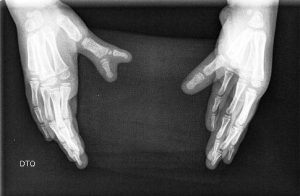

Fig. 3: Polidactilia Cubital (5º dedo)

Polidactilia cubital ou do 5° dedo.

Polidactilia cubital (ou do 5° dedo)

Também conhecida como polidactilia post-axial

A Polidactilia do 5° dedo tem comportamento semelhante à do Polegar?

Ao contrário do que acontece no polegar, a polidactilia do 5° dedo é mais frequente na raça negroide; frequentemente existe tendência familiar. Frequentemente é bilateral e também frequentemente está associada a polidactilia do 5° dedo do pé. É frequente vermos crianças com um dedo supranumerário em cada mão e pé.